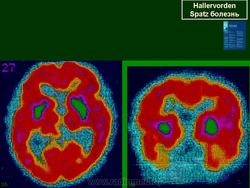

Галлервордена - Шпатца болезнь (J. Hallervorden, 1882-1965, нем. невропатолог; H. Spatz, совр. нем. невропатолог; син. ригидность прогрессирующая) - наследственная болезнь, связанная с нарушением обмена железа и липидов, проявляющаяся в возрасте 7-9 лет повышением мышечного тонуса, гиперкинезами, прогрессирующей деменцией, снижением зрения и пигментным ретинитом; наследуется по аутосомно-рецессивному типу.

Болезнь Галлервордена - Шпатца - наследственное заболевание экстрапирамидной системы, связанная с нарушением обмена железа и липидов и повреждением бледного шара и черной субстанции. Тип наследования аутосомно-рецессивный. При патоморфологическом исследовании характерным признаком является гиперпигментация бледного шара и черной субстанции. Обнаруживается пигментация коры полушарий большого мозга и таламуса. Пигмент находится внутри невронов и глиальных клеток, расположенных около сосудов; содержит железо (вместе с тем каких-либо нарушений обмена железа в организме не обнаружено). Наблюдаются утолщение и фрагментация аксонцилиндров в пораженных областях. Постепенно наступает дегенерация невронов коры полушарий большого мозга и мозжечка. Характеризуются нарастающей экстрапирамидной ригидностью, гиперкинезами (атетоз, торсионная дистония), затем развивается акинетико-ригидный синдром, пирамидная микросимптоматика, снижение интеллекта. Течение медленно прогрессирующее на протяжении 10 - 20 лет.

"Глаз тигра"-наглядно и красиво.